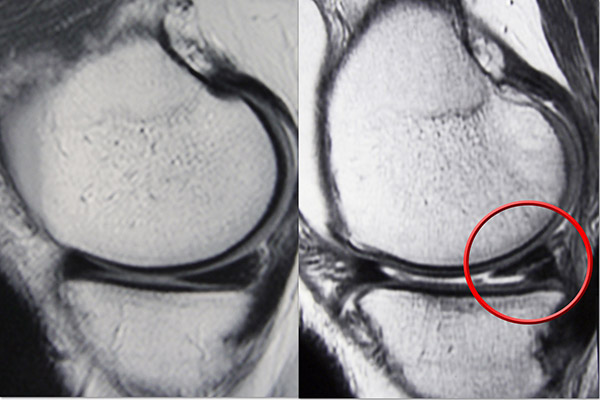

Healthy and Torn Meniscus

MRI scans show (Left) a normal meniscus and (Right) a torn meniscus. The tear can be seen as a white line through the dark body of the meniscus.

Images courtesy of Stuart J. Fischer, MD, FAAOS